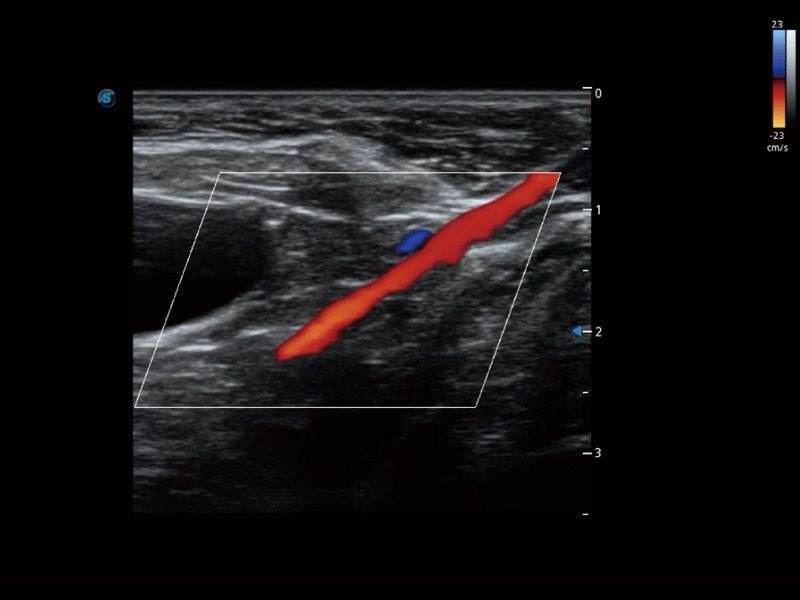

通过创新的 Matrix E自适应滤波器和超长时间域算法,极大提升超低速微细血流的检出能力,同时更精准地滤除软组织和噪声信号,为兽用医生提供以往无法通过常规血流获得的疾病诊断信息。

通过色彩血流和实时宽景相结合,可观察到完整的静脉或动脉的血流,方便医生检查。实时扫查过程中,如有任何操作失误也可以很容易地进行回扫擦除,而不会中断扫查。

采用红、橙、黄、绿、青、蓝、紫这七种肉眼最为敏感的色彩,直观地显示组织内血流灌注的时间先后信息,更精准捕捉血流灌注走行细节。